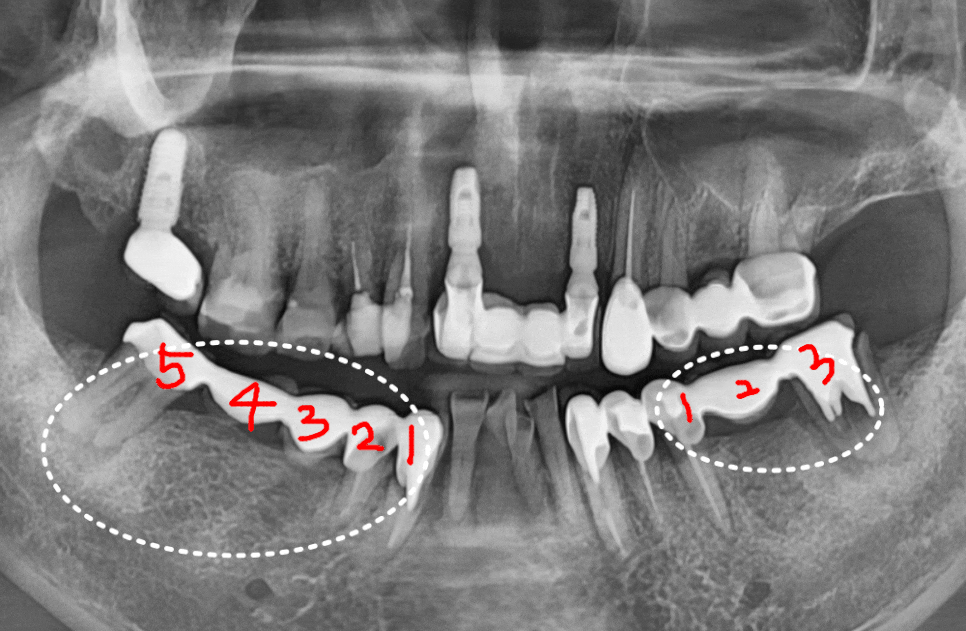

이 환자분은 오른쪽 아래,

무려 5개의 치아를 연결한

긴 브릿지가 통째로 빠져서 오셨는데요.

250507

무엇보다 브릿지를 지탱하던

앞 치아(#43)는

과도한 힘을 버티지 못하고

치아 반쪽이 깨져 있었습니다.

맨 끝 치아(#47) 역시 뿌리 끝에

고름주머니가 크게 잡혀 있었죠.

결국, 남아있는 뿌리 3개를 발치하고

튼튼한 임플란트 3개를 식립하는 것으로

치료 방향을 잡았습니다.

반대편인 왼쪽 어금니 브릿지(#35~37)마저

탈락해버렸어요.

살펴보니 이곳 역시 잇몸 뼈가 녹아내려

치아가 심하게 흔들리고 있었습니다.

왼쪽 역시 살릴 수 없는 치아를 정리하고,

임플란트로 진행했습니다.